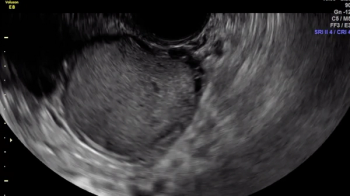

Large rectal deep endometriosis nodule completely fixed to the fundus of a retroverted, retroflexed uterus, resulting in complete rectouterine pouch obliteration (negative sliding sign).

Viewers should focus their eyes on the area closest to the probe, the vagina. With the application of pressure, the operator is attempting to understand whether the bowel is tethered, which it is (demonstrated by the acute angle of the rectal wall muscularis being pulled toward the area of the deep endometriosis nodule).